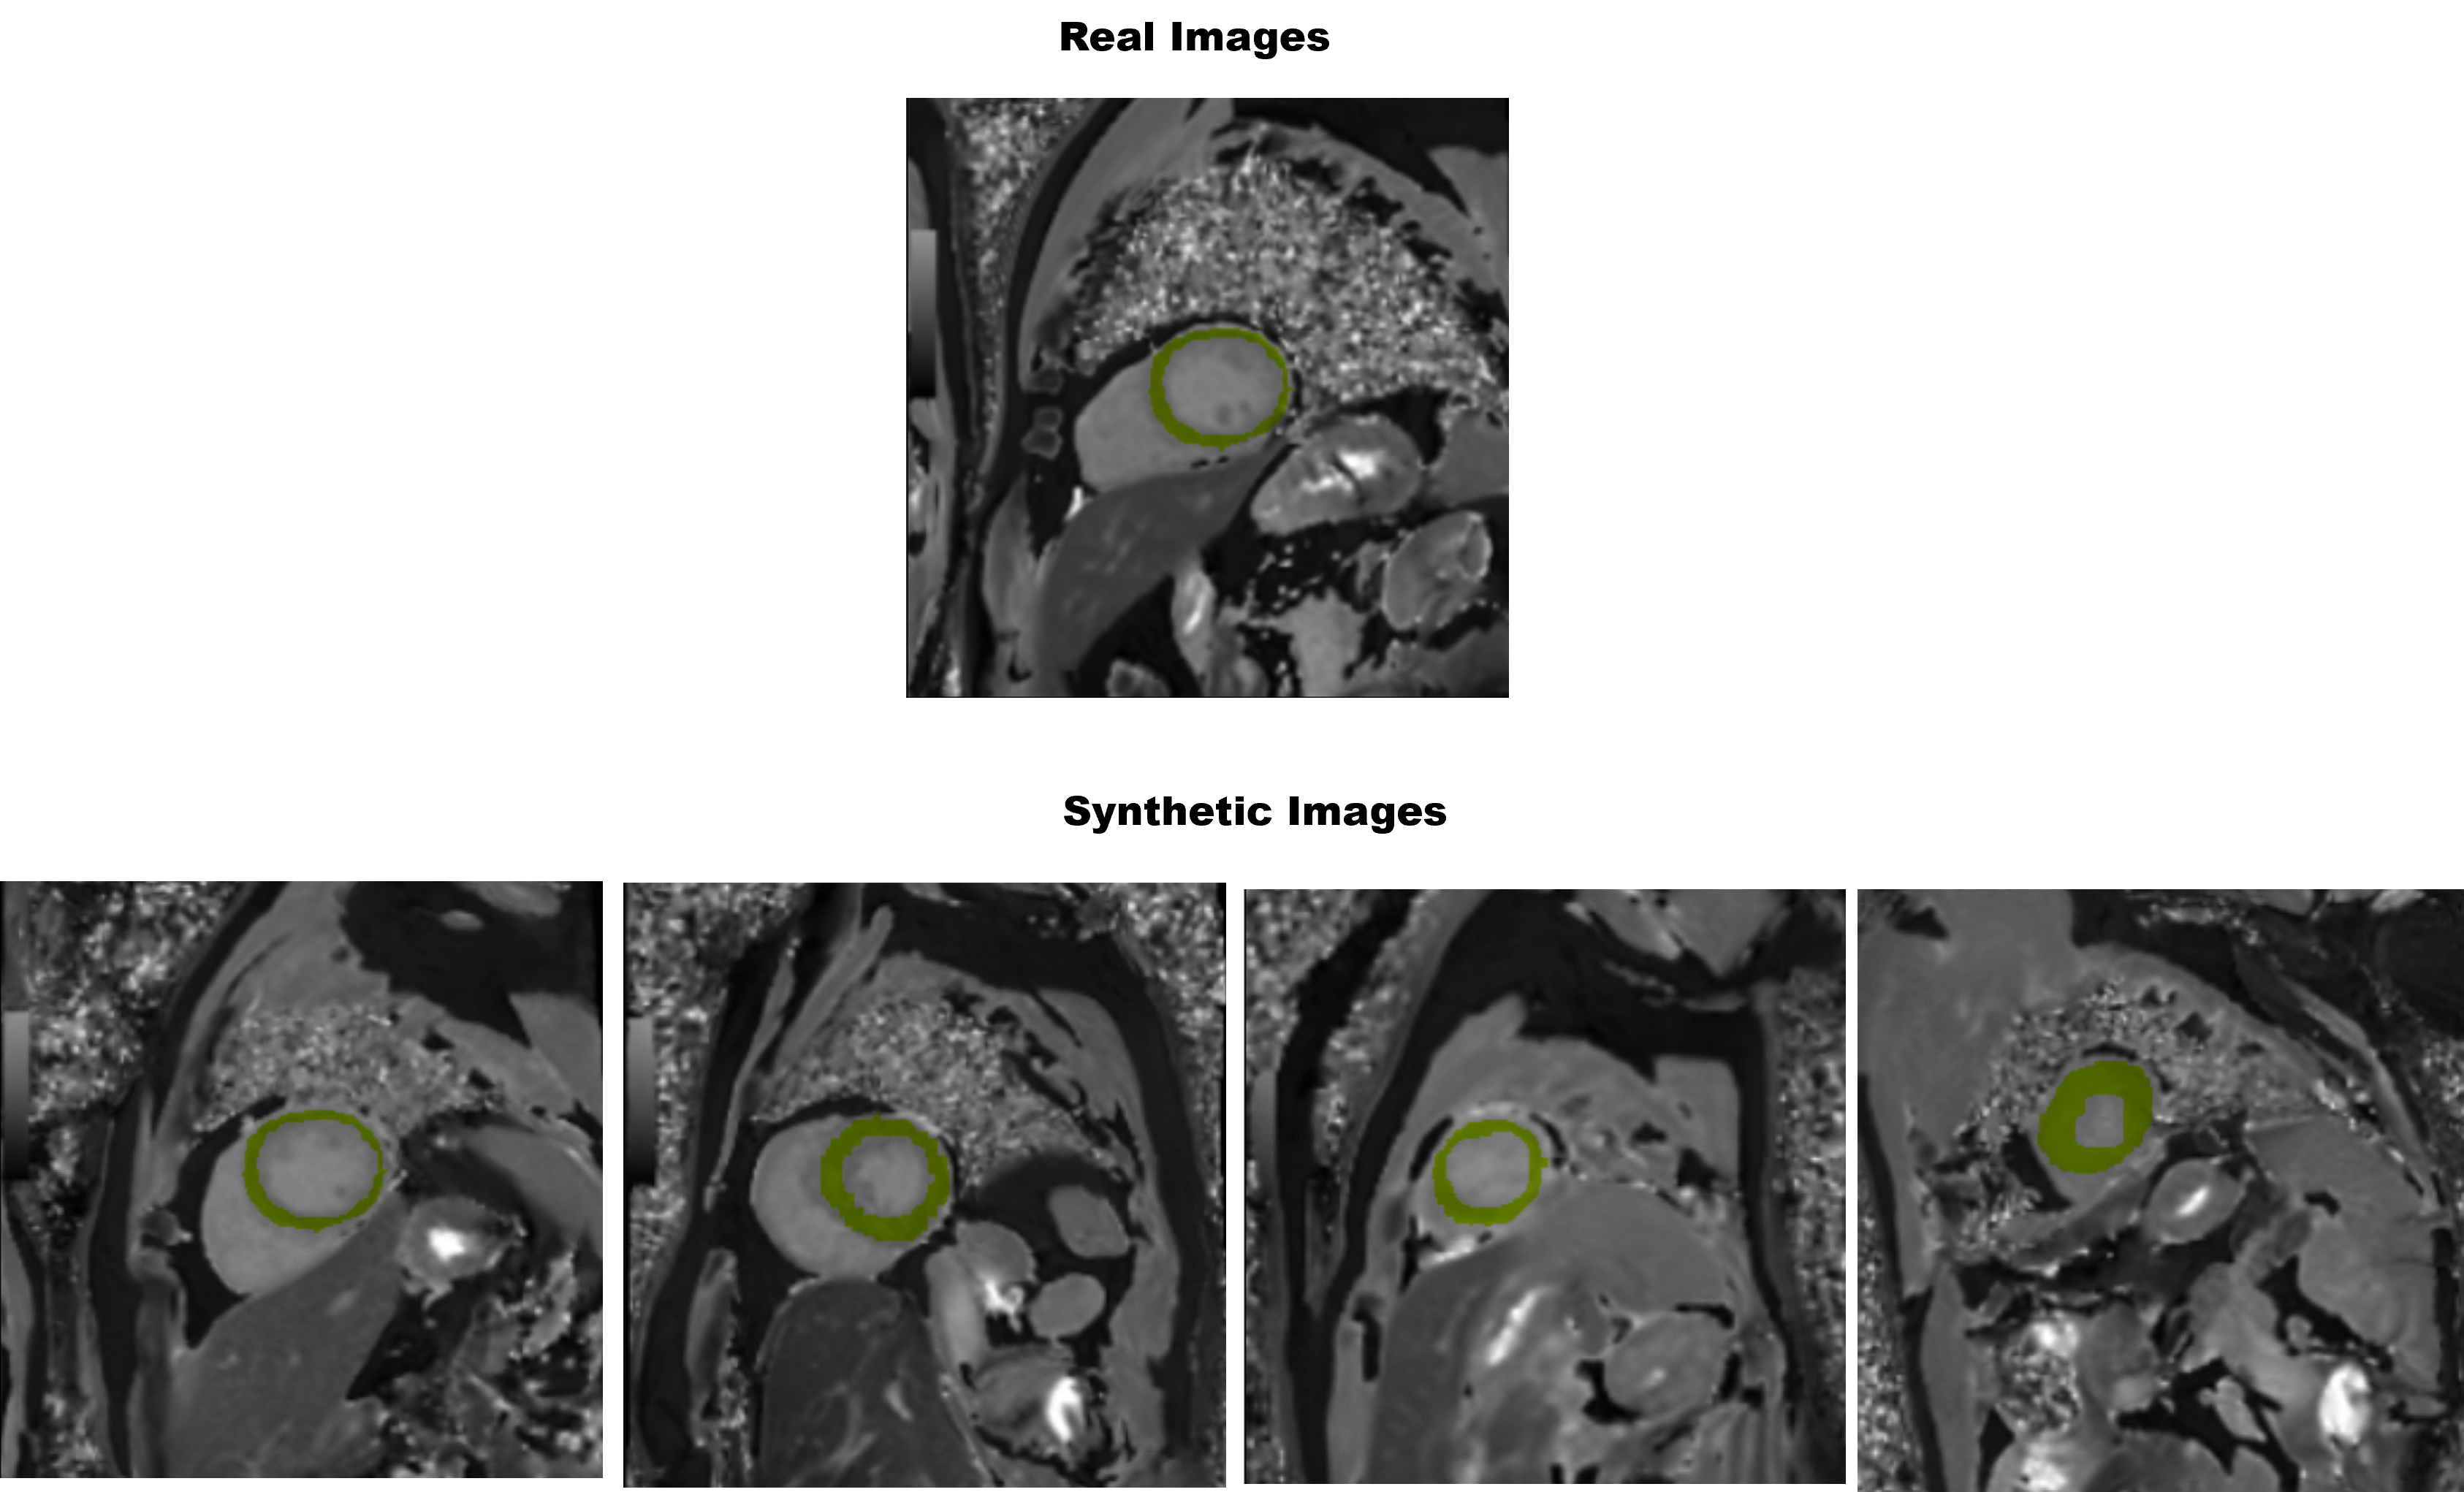

Figure 2: Example real and synthetic images.

Example real and synthetic images are shown in Fig 2. Segmentation results measured by DICE scores are summarized in Table 1. syn.B represents the synthetic data generated using the diffusion model trained on hospital B data. Histograms of the real and the synthetic images are shown in Fig 3 where both the whole image and the myocardium region, which is the segmentation target region were analyzed.